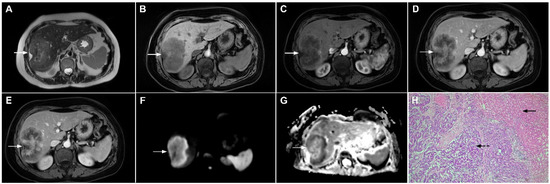

HEH may be of three different pathological types: single nodular, multifocal nodular, and diffuse type. The most common presentation is in the form of multiple, subcapsular nodes located in lesions that coalesce during the course of the disease [100]. Although multifocal nodular and diffuse types of HEH show characteristic radiological findings such as subcapsular localization, capsular retraction, and targetoid appearance on postcontrast study, the diagnosis of solitary HEH represents a diagnostic challenge [102]. Solitary lesion is the least frequent type of HEH and may closely resemble mICC [103]. Both lesions are heterogeneously hyperintense in T2-weighted images and hypointense in T1-weighted images [104]. With regard to tumor vascularity, Kim et al. have shown that solitary HEH usually shows minimal or rim-like enhancement in the early phase and delayed gradual fill-in, which is also a common vascular behavior of mICC (Figure 21). Moreover, both lesions may cause capsular retraction. In such difficult cases, the presence of the “lollipop sign” may suggest HEH [105]. This occurs when a well-defined liver nodule directly invades the vascular structure, resulting in its cut-off, which all together resembles the lollipop [105]. Furthermore, epidemiological data such as higher incidence in middle-aged females and normal values of CA 19-9 might be helpful in differential diagnosis, suggesting HEH [102]. On the other hand, if biliary dilatation is present adjacent to the tumor, the diagnosis of mICC is probable. The use of hepatobiliary contrast agents might be helpful in distinguishing between HEH and mICC, since mICC may show cloud-like appearance with central hyperintensity and peripheral hypointensity in the hepatobiliary phase, while it is rarely seen in HEH [102]. From the standpoint of treatment, the gold standard is radical surgical resection for both mICC and solitary HEH, thus preoperative differential diagnosis is not always necessary.

Figure 21.

Hepatic hemangioendothelioma in a 44-year-old woman. The axial T2-weighted FS image (A) shows a heterogeneously hyperintense lesion (arrow) in liver segment VII, which is causing a slight capsular retraction. In the plain T1-weighted image (B), the tumor is hypointense. Another smaller lesion is also seen in liver segment II (dashed arrow). After administration of intravenous contrast media, there is only subtle perilesional enhancement in the arterial phase (C) with a gradual centripetal enhancement in the portal venous (D) and delayed phases (E). The tumor (arrow) shows high signal intensity in the DWI (F) with low ADC values on the periphery in the corresponding ADC map (G). Hematoxylin and eosin (H&E) staining showed epithelioid hemangioendothelioma (arrows). Normal liver parenchyma is also shown (dashed arrow); original magnification ×40 (H).